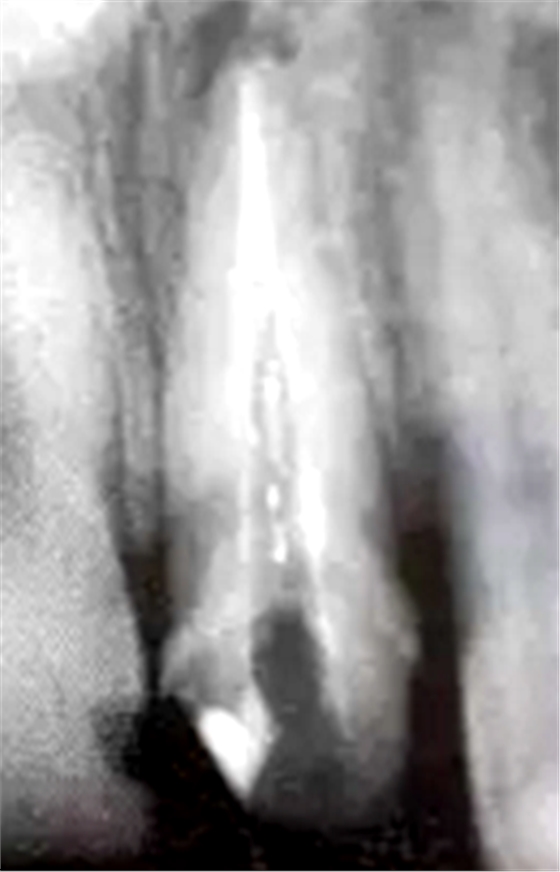

預(yù)備后根管壁上會(huì)不同程度的牙膠和封閉劑等殘留物,所以樁道預(yù)備前后建議X線片輔助檢查預(yù)備深度等情況,而殘留物也會(huì)很清晰地顯現(xiàn)。

根管銼去除殘留物,很難去除干凈,而備取樁道時(shí),禁止使用牙膠溶解劑(如:丁克除、氯仿)等有機(jī)溶劑去除殘留物,以防破壞根尖區(qū)牙膠的封閉和防止附著根管壁影響粘接。

(超聲去除根管殘留物)

通常此時(shí)以超聲潔牙機(jī)更換較細(xì)工作尖進(jìn)入根管(根管消毒沖洗液配合清潔工作后面會(huì)提到),徹底去除樁道根管壁上的附著殘留物,效果明顯。再配合X線片、根管顯微鏡輔助檢查清理的情況下更佳。